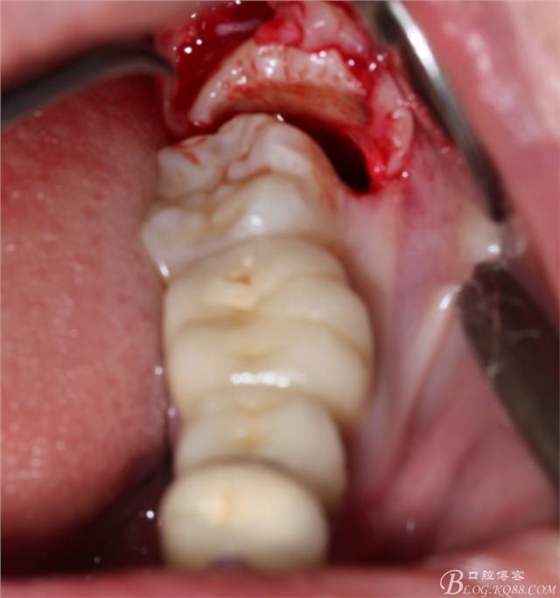

現(xiàn)在都在提倡微創(chuàng),個人看法微創(chuàng)是相對,所當然微創(chuàng)是我們的追求。完全撥出,縫合關閉創(chuàng)口,常規(guī)智齒撥除醫(yī)囑,不適隨診。